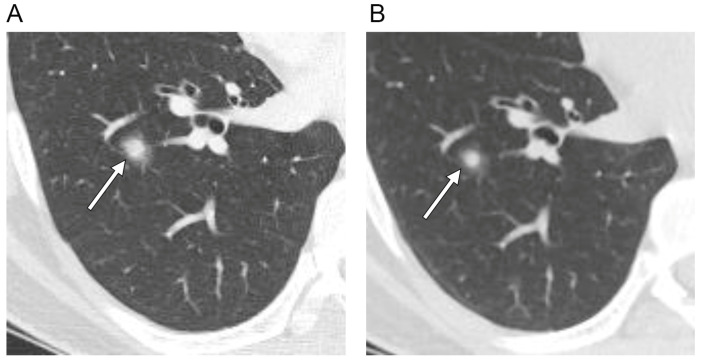

本研究的目的是评价孤立性肺毛细血管瘤(SPCH)的CT和PET-CT表现与临床病理的相关性。本回顾性研究包括来自四所高等院校的17例组织学证实的SPCH患者。本文对SPCH的临床、病理及影像学表现进行综述。评估的CT特征包括病灶位置、大小、密度、轮廓、边缘、增强、支气管充气征的存在、血管周围透光和胸膜缩回,以及PET-CT上的18f -氟脱氧葡萄糖摄取。在随访期间,还评估了大小的变化。影像学表现与临床病理表现相关。患者平均年龄47岁(范围30-60岁)。所有SPCHs都是在筛查CT检查(n = 13,76%)或癌症检查期间偶然发现的(n = 4,24%)。大多数SPCHs表现为半实性结节(n = 15.88%),其余分别表现为纯磨玻璃结节或纯实性结节。大多数具有平滑轮廓(n = 16.94%),而一个具有分叶状轮廓。9家SPCHs(53%)的利润率不明确。10例(59%)SPCHs存在空气支气管征,2例(12%)血管周围透光。所有SPCHs在增强CT上表现为低衰减,在PET-CT上表现为低代谢。在随访期间(平均14.8±17.7个月),10例(59%)SPCHs病变大小和密度无变化,3例(18%)SPCHs病变大小和密度减小或波动。SPCH常在中青年偶然发现,通常表现为不明确的部分实性结节,CT上可伴有支气管充气征、血管周围透光、大小或密度波动,PET-CT上可伴有代谢低下。

The aim of this study was to evaluate the CT and PET-CT features of solitary pulmonary capillary hemangioma (SPCH) with clinicopathologic correlations. This retrospective study included 17 patients with histologically proven SPCH from four tertiary institutions. The clinical, pathological and imaging findings of SPCH were reviewed. The CT features assessed included lesion location, size, density, contour, margin, enhancement, presence of air bronchogram, perivascular lucency and pleural retraction, and 18F-fluorodeoxyglucose uptake on PET-CT. Changes in the size during the follow-up period were also evaluated. Imaging features were correlated with the clinicopathologic findings. The mean age of the patients was 47 years (range 30-60 years). All SPCHs were incidentally detected during screening CT examinations (n = 13, 76%) or during cancer work-up (n = 4, 24%). Most SPCHs appeared as part-solid nodules (n = 15, 88%), the remaining appeared as a pure ground-glass nodule or a pure solid nodule, respectively. Most had smooth contours (n = 16, 94%), while one had a lobulated contour. Nine SPCHs (53%) showed ill-defined margins. Air bronchogram was present in ten (59%) SPCHs, and perivascular lucency in two (12%). All SPCHs exhibited hypoattenuation on contrast-enhanced CT and hypometabolism on PET-CT. During the follow-up period (mean 14.8 ± 17.7 months), the lesions showed no change in size or density in ten SPCHs (59%), decreased or fluctuation in size and density in three (18%). SPCH is often incidentally detected in young and middle-aged adults, commonly as an ill-defined part-solid nodule that may accompany air bronchogram, perivascular lucency, and fluctuation in size or density on CT and hypometabolism on PET-CT.